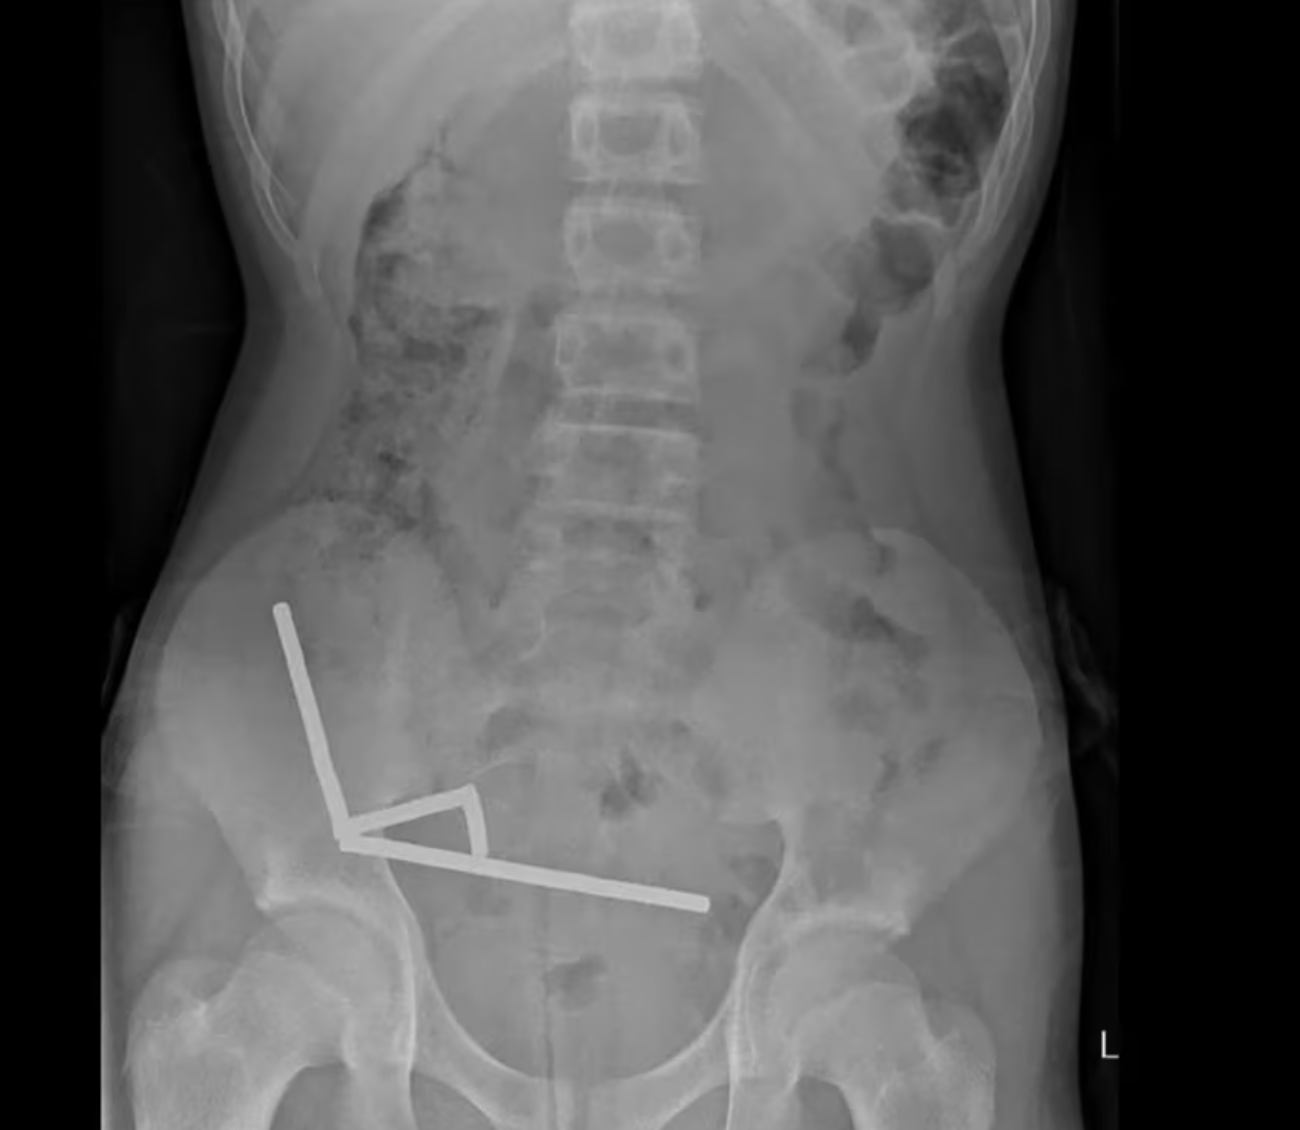

Phim chụp X-quang cho thấy các nam châm hút nhau trong bụng cậu bé. Ảnh: Tạp chí Y khoa New Zealand

Trước khi được đưa đến bệnh viện, cậu bé đã chịu đựng cơn đau bụng kéo dài bốn ngày. Tại đây, em cho biết đã nuốt số nam châm này khoảng một tuần trước đó. Kết quả chụp chiếu cho thấy chúng đã kết lại thành bốn chuỗi trong ổ bụng, kéo các đoạn ruột lại với nhau bằng lực từ. Hình ảnh bị nhiễu do từ tính mạnh buộc các bác sĩ phải tiến hành phẫu thuật khẩn cấp.